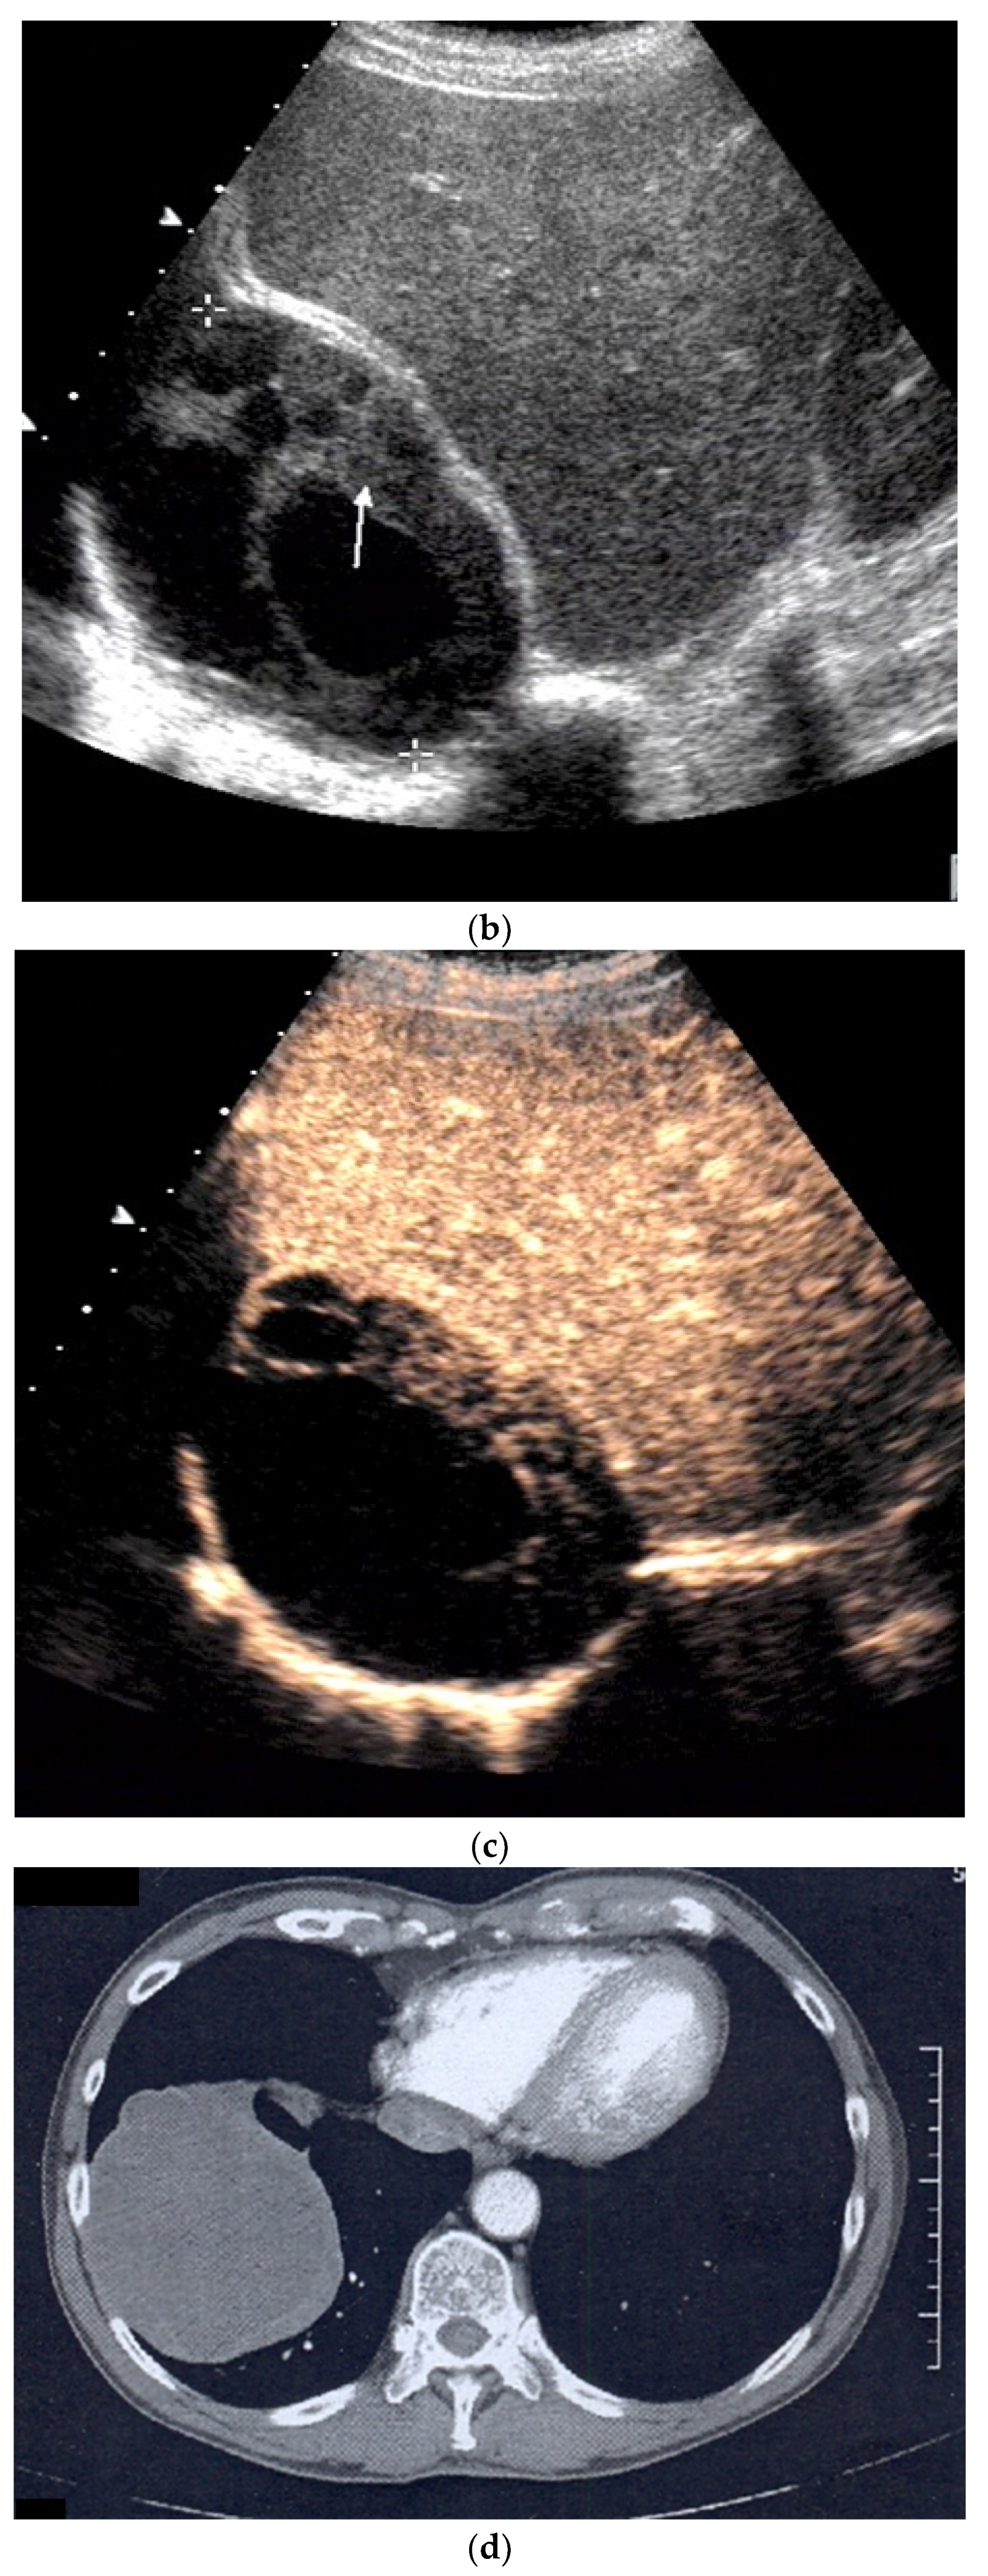

| Splenosis | Round, homogeneous lesions. Macrovessels on CDI are possible. Spleen-typical contrast behavior in CEUS with long-lasting contrast enhancement over several minutes. |